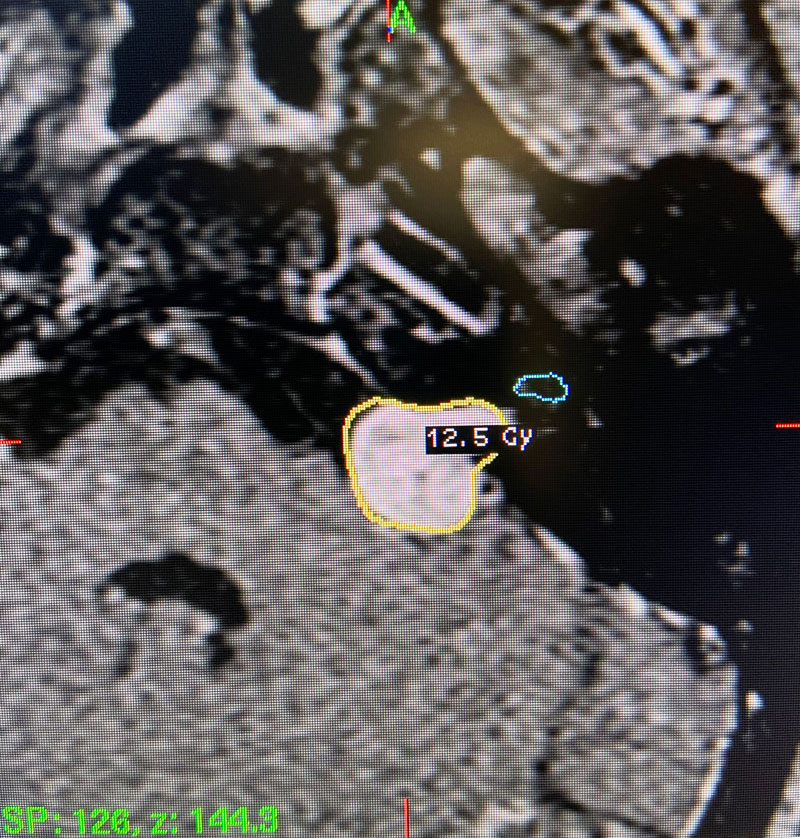

Image 2: Intra-operative Gamma Knife treatment planning for the left acoustic neuroma. A tightly conformal treatment is set for 12.5Gy to the 50% isodose line. The cochlea has also been contoured, based off a fused image from a fine cut T2 sequence.

This patient: This patient had a moderate sized , symptomatic acoustic neuroma with serviceable hearing. Gamma Knife was recommended. A Gamma Knife treatment was performed by Dr. Michael Brisman. The radiation oncologist was Dr. Leester Wu. A treatment plan was made that was very conformal to the tumor. A prescription of 12.5Gy to the 50% isodose line was delivered. This plan involved a mean cochlear dose of 3.5Gy.

Technical Aspects of Gamma Knife Treatment: Dose to the tumor is set to 12-13 Gy to the edge of the tumor. The 50% isodose line is set to the edge of the tumor. Dosing under 12Gy is less effective at tumor control, and dosing over 13Gy puts the facial nerve at risk. There is evidence that the radiation dose to the cochlea affects whether hearing will ultimately be preserved. As such, if there is meaningful hearing at the time of treatment, the mean cochlear dose should be set to 4.2Gy or less. The cochlea is separately contoured at the time of treatment off fine cut T2 sequences which are then fused to the post contrast T1 images.